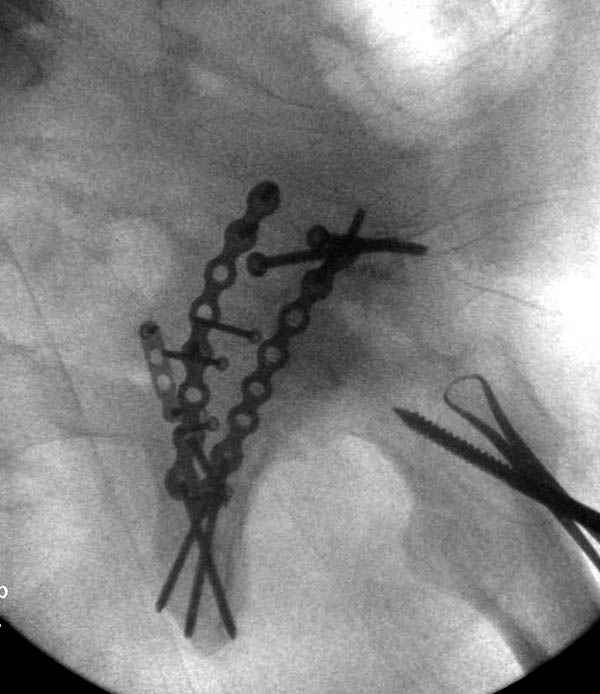

Из-за большого обьема конечности доступ к бугорку был затруднен, предварительно зафиксированный шуруп не удержал бугорок, поэтому фиксацию провели толстыми нитками. Состоятельность фиксации бугорка обычно проверяем во время операции, под рентген контролем проводится движения конечности, особенно приведение.

По возможности вышлите снимки, сканы таза до

реконструкции, интраоперационные.

По снимку создается впечатление о высоком поперечном переломе, задней колонны, стенки; почему не пользовались *magic screw*?

Там множество обычных 2.7 мм шурупов, потом идет фиксация основными пластинами.

Снимки здесь....